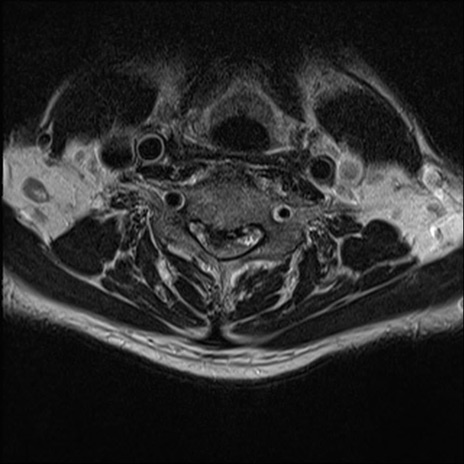

【整形】TIPS症例7 頚椎MRI T2WI(横断像)

頚椎MRI

矢状断像と横断像